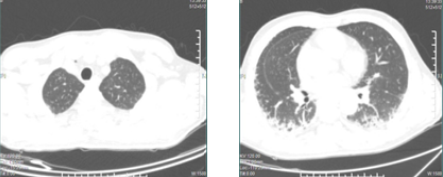

通过全科室医护人员的共同努力,患者的皮下气肿、纵膈气肿逐渐吸收,2018年4月3日复查胸部CT(见下图),患者的皮下积气、纵隔积气较前明显吸收减少,双肺间质性肺炎无明显变化,目前病情稳定,拟近日出院。